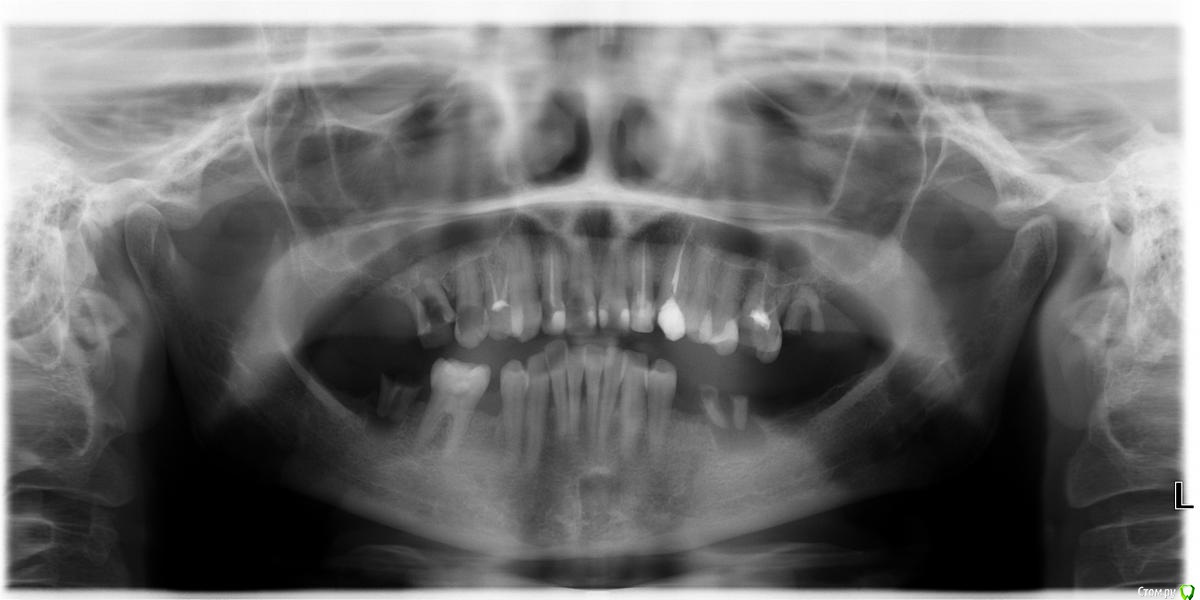

shanti.natalia Опубликовано 21 февраля, 2015 Поделиться Опубликовано 21 февраля, 2015 (изменено) Необходимо мнение экспертов по максимальному сохранению правого верхнего переднего зуба, что максимально можно и необходимо сделать ? панорамный снимок приложен. Изменено 21 февраля, 2015 пользователем shanti.natalia Ссылка на комментарий

shanti.natalia Опубликовано 21 февраля, 2015 Автор Поделиться Опубликовано 21 февраля, 2015 У Вас есть прицельный снимок?есть КТ Ссылка на комментарий